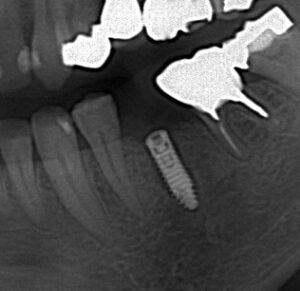

抜歯後インプラントを埋入しましたが骨が足りずネジが

見えています。

人工骨を填入しメンブレンを敷いたところです。

レントゲンでは外側に人工骨を足したため

像としては現れにくいです。